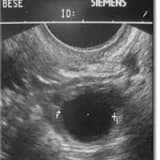

‘Balanslama Tekniği’ uygulaması yumurta, embriyo ve rahim iç zarında çeşitli hastalık ve problemlerle ortaya çıkan ve gebelik şansını azaltan olumsuzluklarda kullanılmaktadır. Kadının kendine ait yumurtalık ve kan hücreleri ile onlara ait özel maddeler içeren sıvıların kullanılması ile ortadan kaldırılarak pozitif yönde dengelenmesi üzerine dayanmaktadır.

Yukarıda sayılan hastalıklar nedeniyle yumurtaların yumurtalıklarda gelişmesi sırasında maruz kaldıkları uygunsuz ve düzensi ortam hormonları etkilemekte, bağışıklık sistemindeki yetersizlikler onların gelişmelerini ve olgunlaşmalarını geciktirmektedir. Bu gecikme onlara olgunlaşma desteğini sağlayan ve çevrelerinde yer alan özel destek hücrelerinin ve sıvılarının etkilenmesi ve yumurtalara yeterli desteği verememesi durumunda ortaya çıkmaktadır. Sonuçta yumurtanın hem döllenme olasılığı azalır hem de döllenme sonrası oluşan embriyo denilen ileride gebelik oluşturacak hücre kümesinin kalitesini bozulmakta ve rahim iç zarına gömülme kabiliyetini düşmektedir.

Yumurtalar ilaç tedavisi ile geliştirilip yumurtalıklardan alındıktan sonra dölleme için özel olarak hazırlanır. Bu sırada yumurtalarla gelişme sürecine girmiş olan ve onları çevreleyen özel destek hücreleri ve sıvıları ayrıştırılır. Bu destek hücreleri laboratuarda ayrı bir sistemle değerlendirilir ve uygun olan hücre grupları tespit edilir. Uygun olan hücreler kendi sıvıları ve geliştirilmiş besleme ortamlarında çoğaltılma işlemine bırakılır. Bu hücreler gelişme ve çoğalmalarına devam ederek 24-36 saat içinde embriyolara önemli pozitif katkı sağlayacak hale gelirler. Aynı zamanda yumurtalar mikroskoplar altında seçilmiş DNA kırılmaları en az spermlerle döllenir. En iyi şartlarda döllenmiş yumurtalar gelişmiş destek hücrelerinin ve sıvılarını içine konarak kendilerine sağlanan özel madde ve hormonların etkisiyle en iyi olgunlaşma düzeyine eriştirilmeye çalışılır. Embriyo izleme sistemi aracılığıyla belirlenen en kaliteli yumurtalar seçilir.

Döllenmeyi takiben 3 . günde gelişen destek hücrelerinin saldıkları LIF ve PAF gibi maddelerin embriyoların rahim içine gömülmesini sağlayacak düzeye eriştirdiği saptanmıştır. Bu şekilde yumurta ve embriyolardaki sorunlar dengelenmiş; ‘Balanslanmış’ olmakta ve embriyo rahim içine gömülecek hale gelmiştir.

3. Rahim içinde bağışıklık sistemi ile ilgili bir mekanizma gebeliği sağlamakta ve onun sağlıklı şekilde devamını desteklemektedir. Yukarıda belirttiğimiz hastalıklar ve durumlar rahim içi zarının embriyoları içine almasını engellemekte ve gömülemebilme işlevini azalmaktadır. ‘Balanslama Tekniği’nde rahim içindeki azalmış gömülgenlik kadının kanında bulunan özgün bağışıklık sistemi hücrelerinin kullanılması ile arttırılmaktadır. Bu hücreler yumurta toplama sırasında alınan kandan ayrıştırılmakta ve yine özel üreme ortamlarında çoğaltılmaktadır. Bu çoğalma sırasında hücrelerden rahim içinde gebeliğin oluşmasını sağlayacak uygun bağışıklık ortamı oluşturacak maddeler salınmakta ve toplanmaktadır. Ayrıca bu hücreler rahim içine konduklarında bir süre pozitif etki sağlayan maddeleri salmaya devam etmektedirler. Sonuç olarak elde edilen sıvıların ve hücrelerin embriyoların rahim içine yerleştirilmesinden önce rahim içine verilmesiyle rahim içinin ortamı embriyolara karşı gömülebilir diğer bir deyişle ‘Balanslanabilir’ hale getirilmektedir.